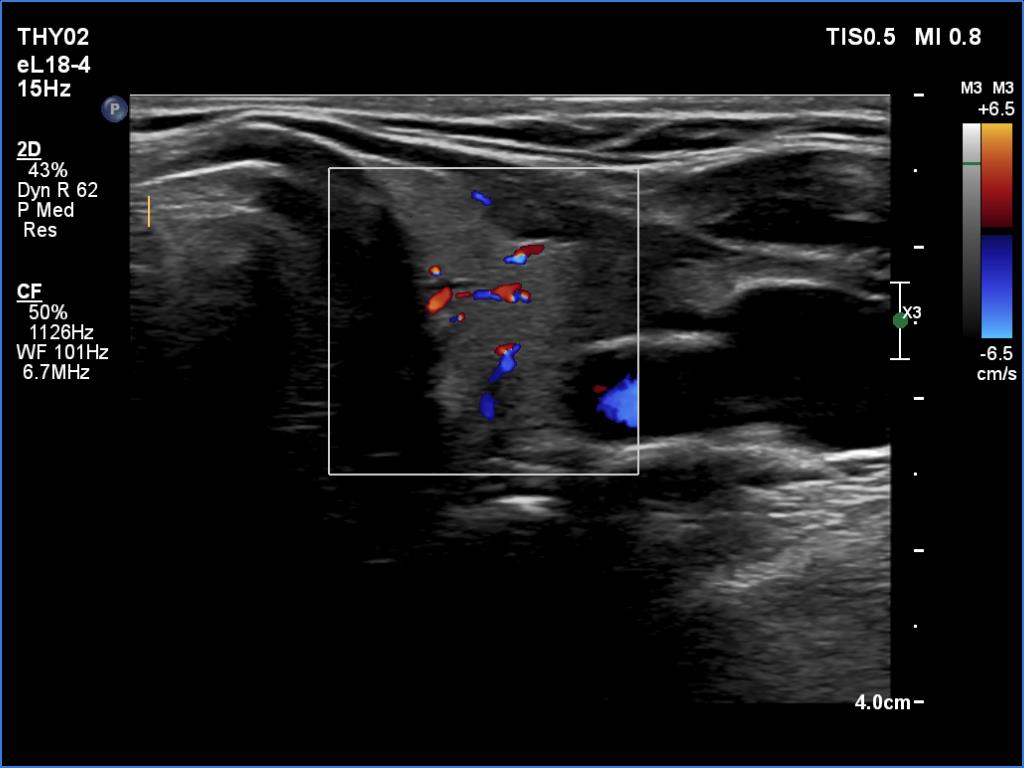

Left lobe, transverse scan, color Doppler mode. The vascularity is average.